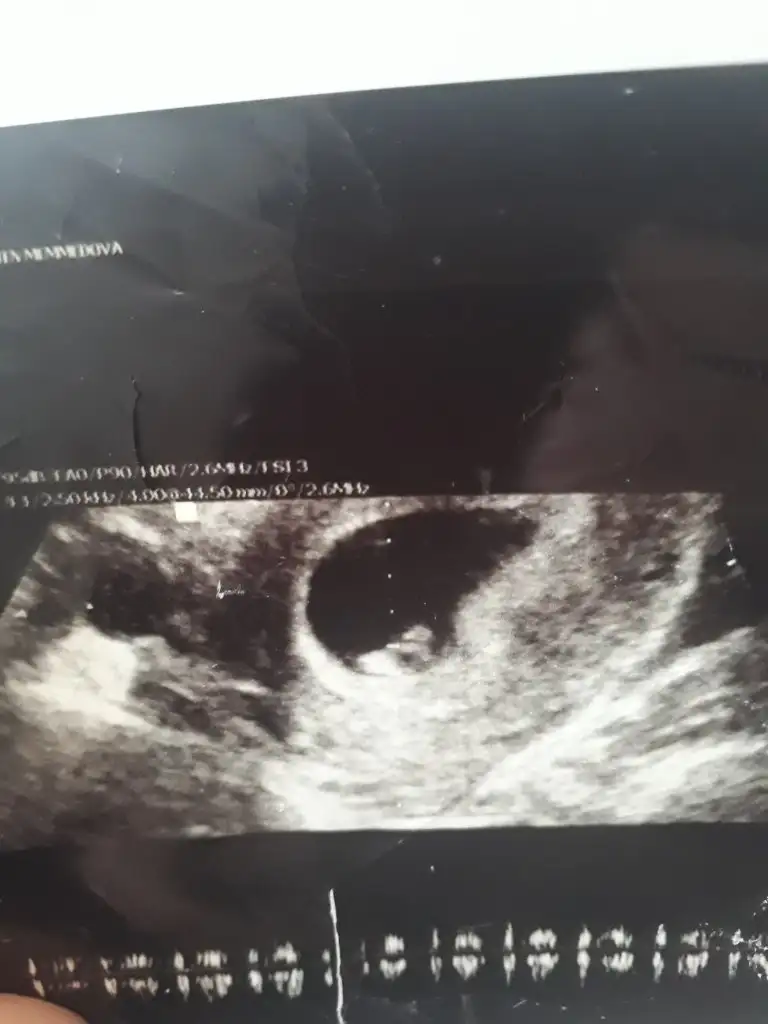

Merhaba arkadaşımın bebeği için cinsiyet yorumlarmısınız ☺️☺️

Eklentiler

• F17F74DB-0A55-4017-AE3F-ACD7B369930D.webp

F17F74DB-0A55-4017-AE3F-ACD7B369930D.webp

21,2 KB · Görüntüleme: 47